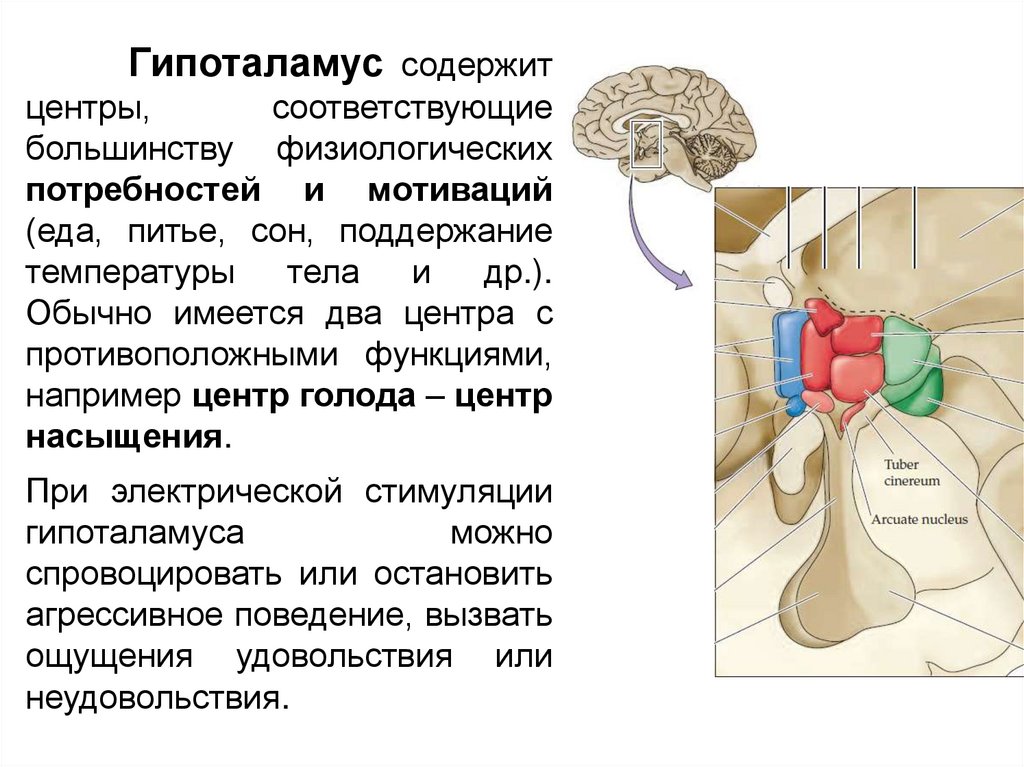

Как работает центр насыщения в гипоталамусе: визуальные иллюстрации